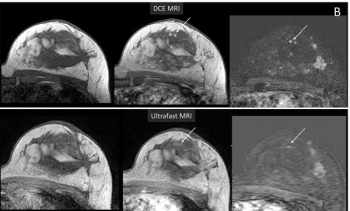

New research findings suggest that image quality and lesion conspicuity are significantly lower with ultrafast breast MRI in comparison to standard dynamic contrast-enhanced breast MRI.